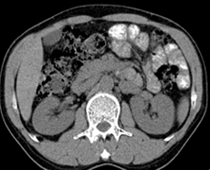

患者,男,57,常年不吃午饭,近一个月来腹部隐痛,无明显黄疸,明天进行增强扫描,图象另上传,麻烦各位帮忙一起看看讨论讨论

肝外胆管扩张,胰头增大,肠系膜上静脉似有包埋征象。

考虑:胰头占位性病变,建议增强进一步检查。

肝外胆管稍扩张,胰腺钩突略增大,但外形尚可,境界清楚。(常年不吃午饭)提示胰腺炎可能大,肿瘤第二步考虑。

支持考胰头占位性病变,感觉十二指肠壁不规则增厚,不排除十二指肠降部占位可炎症

胰头增大,胆总管增宽,考虑胰头癌可能性大,明天看增强片有助诊断.